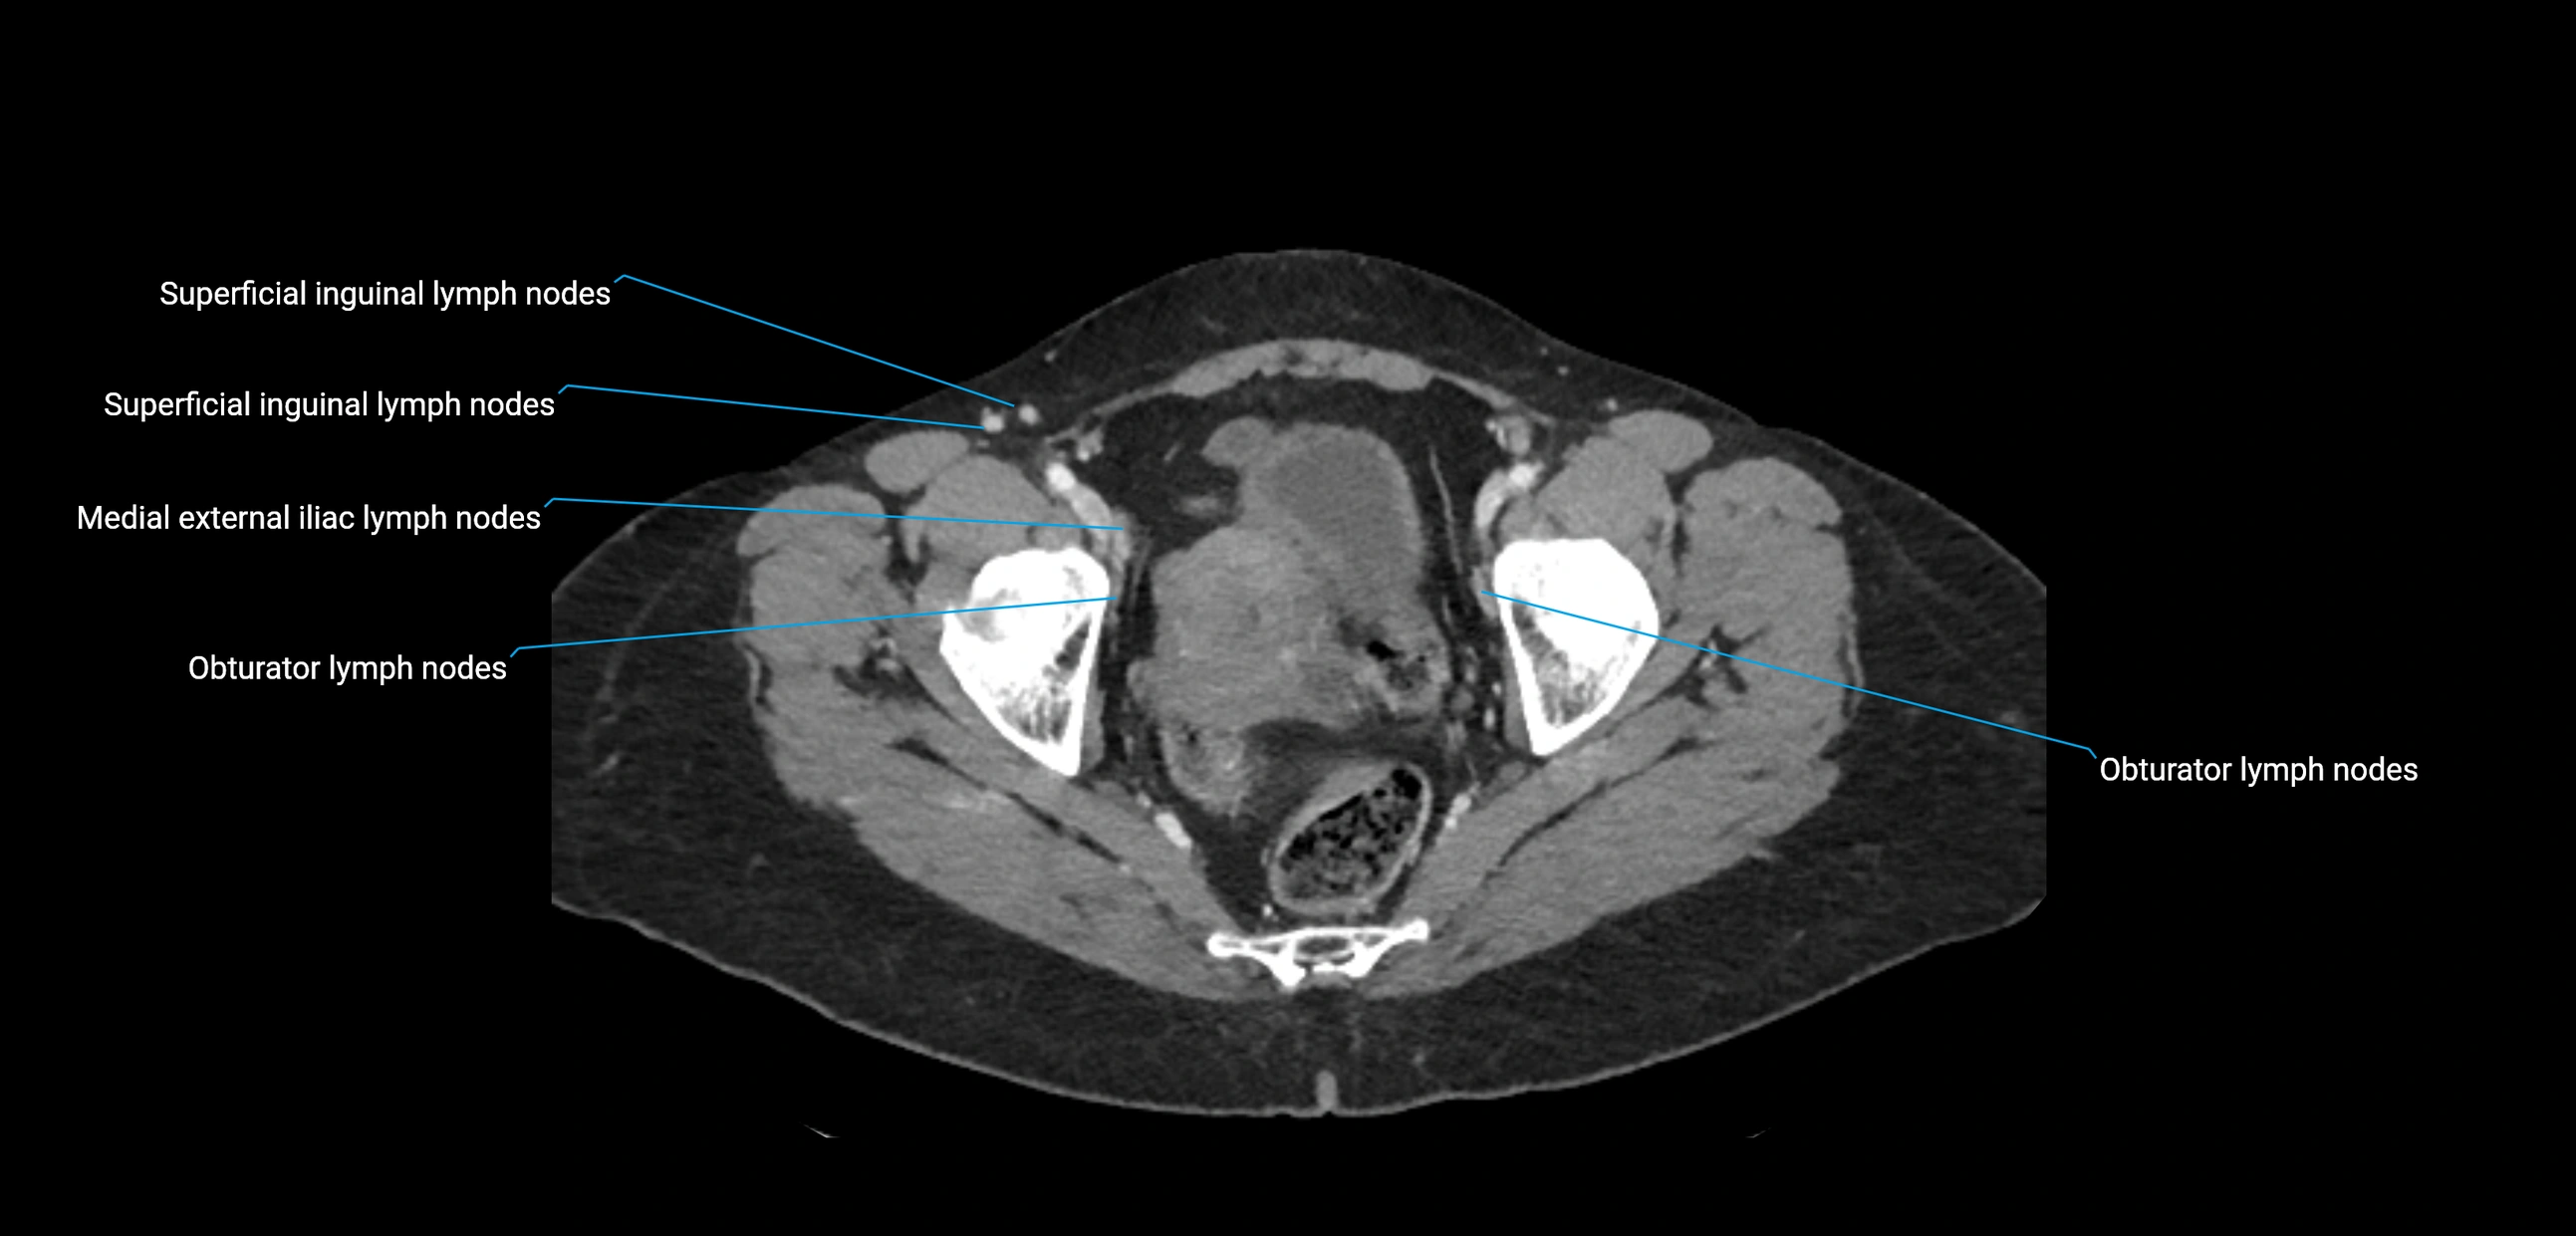

CT Appearance

CT Pre-Contrast:

• Nodes appear as soft-tissue density nodules adjacent to the aorta and IVC

CT Post-Contrast:

• Normal nodes enhance homogeneously

• Malignant nodes may show heterogeneous enhancement, central necrosis, or conglomerate formation

• Size >1 cm short axis is suspicious, though morphology and distribution are equally important